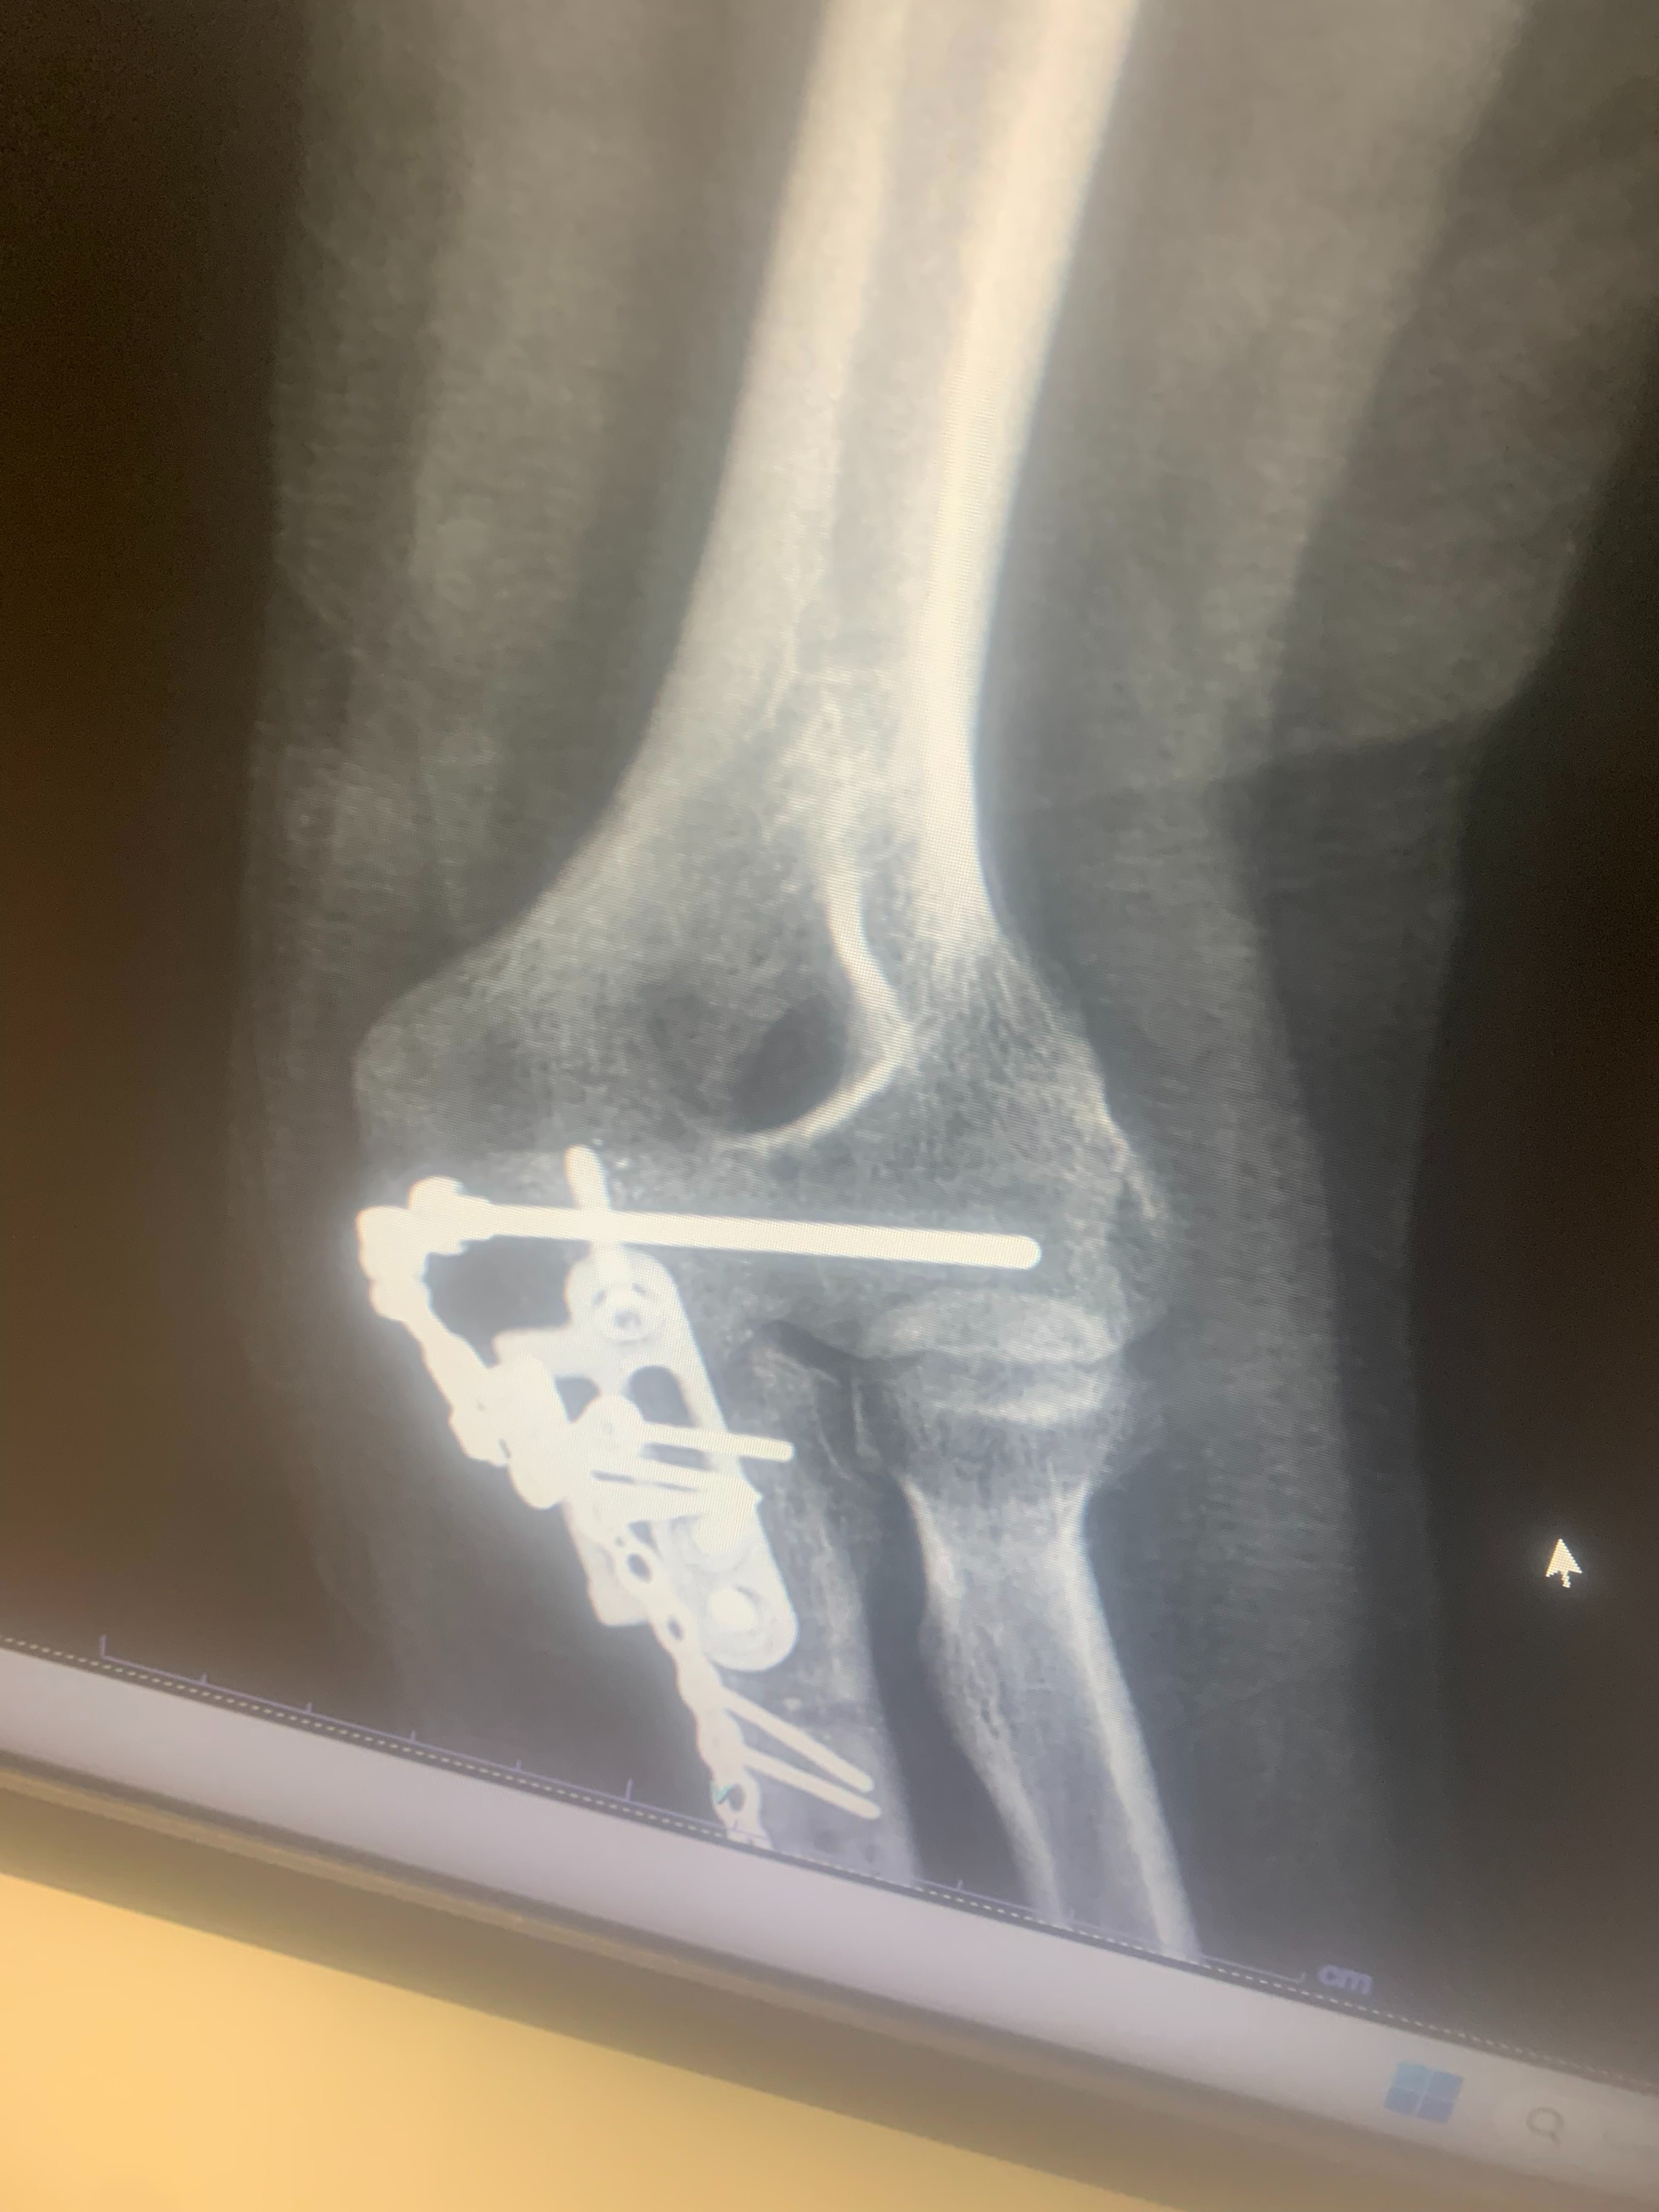

Since the accident, Blake has undergone four surgeries and is still in the long process of recovery. After the second surgery, he developed a staph infection when some of the hardware in his elbow poked through his skin. He spent five days in the hospital, had a PICC line and portable IV for a month, and had a nurse visit daily to administer medications and clean his wounds. His fourth surgery involved removing most of the hardware, as the staph infection was clinging to the metal. Now, Blake has two metal rods on the outside of his arm held in place by six screws, and his road to recovery is far from over. On top of the physical pain and uncertainty, Blake has been unable to work for six months, which has made it even more difficult to cover mounting medical bills and everyday expenses.